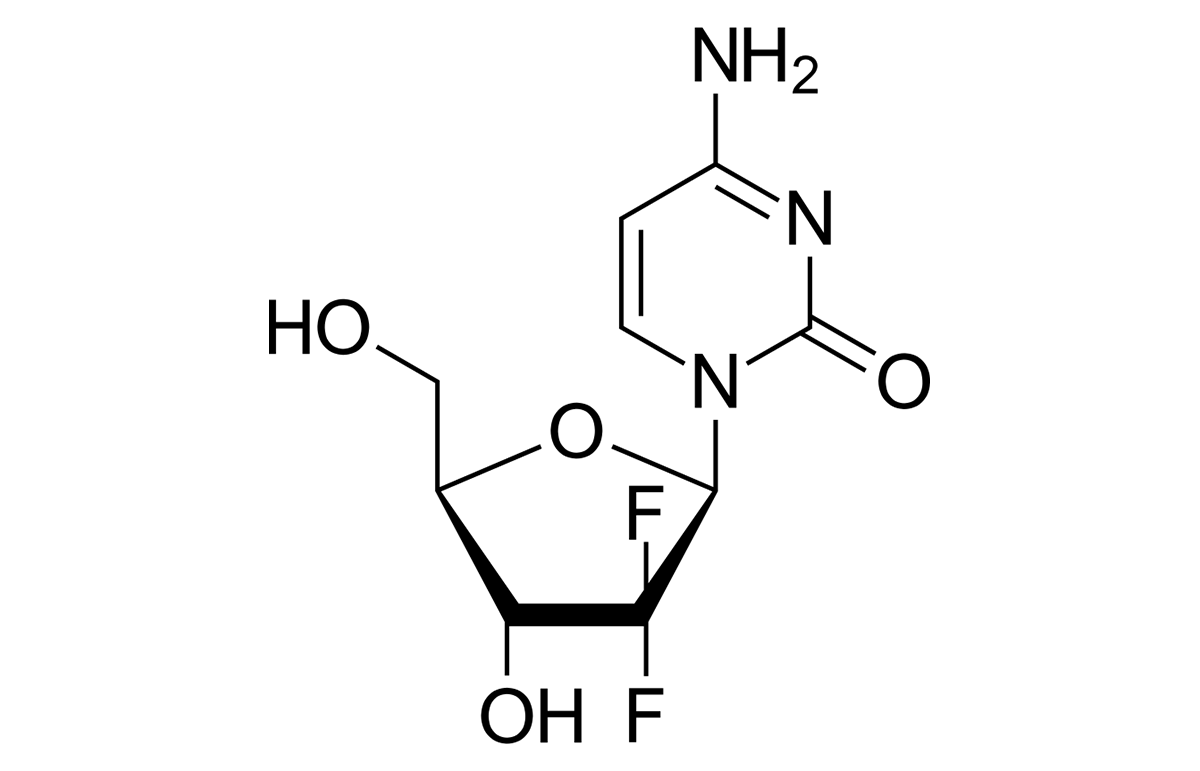

- Leading manufacturer of key anti-cancer APIs.

We continue our focus to bring innovation in Fermentation technologies, Liposomal drug delivery technologies, Lipid based drug delivery technologies, Nanoparticle drug delivery technologies, Synthetic chemistry & High potent cytotoxic products.